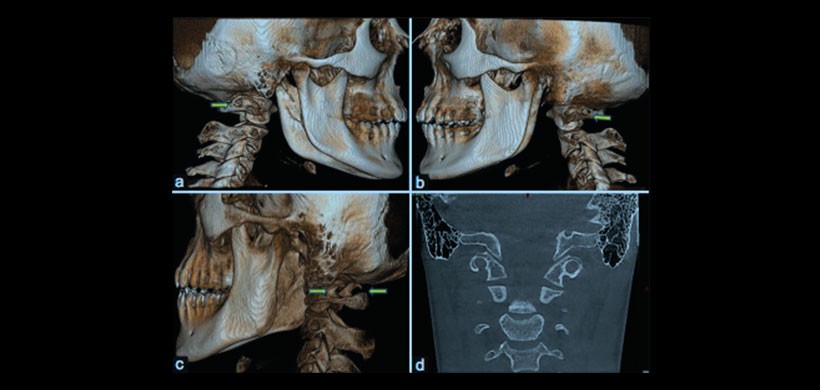

Figura 3: Varios tipos morfológicos de ponticulus posticus vistos en la vista posterior de las imágenes de tomografía computarizada de haz de cono (a-c). Bilateral completo (a y b); bilateral parcial (c) y completa a la derecha y parcial a la izquierda (d)